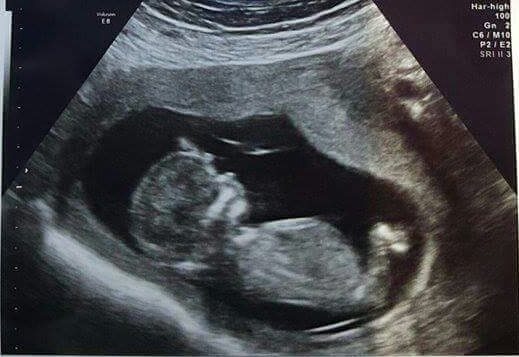

I have had 2 previous ultrasounds already, but my anxiety is really high with this one due to previous losses I called my Dr today. Luckily, my Dr does his own ultrasounds so I don't have to wait for the ultrasound techs, and he was able to get me in this afternoon just to take a look and ease my anxiety. Baby is great, heartbeat is strong and I was able to see baby wiggle a little! Thank goodness my Dr understands and was able to fit me in today! My anxiety dropped so much!

Unexpected u/s today due to the doctor not being able to find the heartbeat with the Doppler. I was super excited to see this LO bouncing around! 14w3d today!